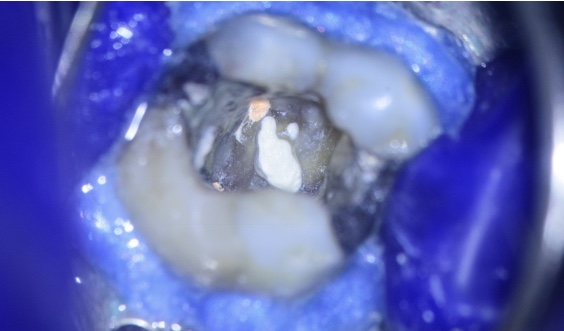

Realizamos a abertura do dente com a broca diamantada esférica de haste longa em alta rotação número 1016. Logo após a abertura, já foi possível localizar a perfuração em assoalho pulpar (figura 3).

Fizemos a desinfecção com hipoclorito de sódio 2,5% e realizamos o fechamento da perfuração.

Antes do vedamento da perfuração, deixamos as bordas da perfuração regulares (não cortantes ou com espículas). Com isso, é possível ter uma regularização da região e das paredes a serem vedadas com o material reparador. Isso pode ser feito com inserto de ultrassom esférico diamantado com irrigação.

Após o preparo das bordas da perfuração, foi realizada a hemostasia da região. Este controle pode se dar com hidróxido de cálcio P.A.

Após a hemostasia, foi secada a região com bolinha de espuma (Pele Tim da VOCO) e inserido o cimento biocerâmico reparador (Bio C Repair – Angelus). Esses cimentos biocerâmicos são bioativos e possuem a capacidade antimicrobiana. Além disso, estimulam a formação óssea no local em questão.